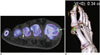

Similarly, synovial hemosiderin deposits can be identified on dual-energy CT in patients with pigmented villonodular synovitis (23). As in intravenously enhanced CT, VNC imaging may be applied to CT arthrography in the musculoskeletal region (23). In the musculoskeletal region, virtual non-calcium imaging may be used to evaluate the bone marrow that is beyond the scope of CT evaluation. Virtual non-calcium imaging subtracts calcium from cancellous bone and allows detection of acute traumatic bone marrow lesions including occult fractures and bone bruises, which cannot be clearly visualized on single-energy CT (23, 24, 25). Diagnostic performance of virtual non-calcium imaging tends to be better for small appendicular bones than axial skeletons. Adjustment of material decomposition ratio (r) is necessary for different tube voltage settings (1.45 for 80 and 140 kVp; 1.3 for 100 and 140 kVp) to eliminate bone mineral completely. Nevertheless, virtual non-calcium imaging is limited in evaluating bone marrow alterations close to the cortical bone or in sclerotic bone. In addition, false-positive results may occur due to the presence of normal red marrow, and other pathologies, such as osteonecrosis or degenerative changes, may mimic post-traumatic bone marrow lesions. A combined review of gray-scale images and color-coded images can facilitate the identification of small attenuation changes within the bone marrow (23, 24, 25). Of note, automatic color-coded bone marrow segmentation is incomplete, especially in the head region.